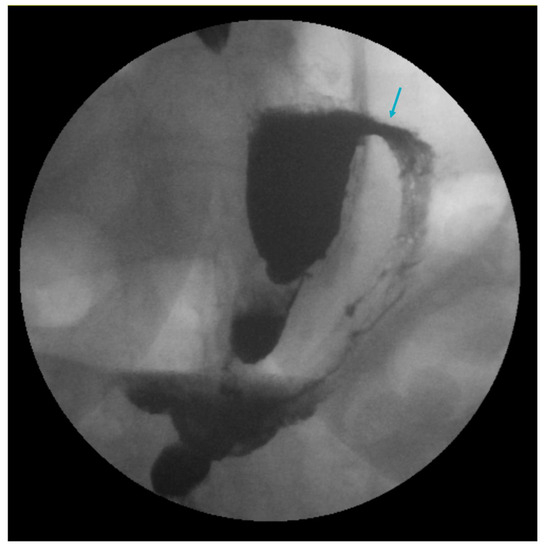

- Filho, A.J.B.; Kondo, W.; Nassif, L.S.; Garcia, M.J.; Tirapelle, R.D.A.; Dotti, C.M. Gastrogastric Fistula: A Possible Complication of Roux-En-Y Gastric Bypass. J. Soc. Laparoendosc. Surg. 2006, 10, 326–331. [Google Scholar]

- Alyaqout, K.; Almazeedi, S.; Alhaddad, M.; Efthimiou, E.; Loureiro, M.d.P. Gastrogastric Fistula after Roux-en-y Gastric Bypass: A Case Report and Review of Literature. Arq. Bras. Cir. Dig. 2020, 33, e1509. [Google Scholar] [CrossRef] [PubMed]

- Wei, M.T.; Ahn, J.Y.; Friedland, S. Over-the-Scope Clip in the Treatment of Gastrointestinal Leaks and Perforations. Clin. Endosc. 2021, 54, 798–804. [Google Scholar] [CrossRef]

- Rogalski, P.; Swidnicka-Siergiejko, A.; Wasielica-Berger, J.; Zienkiewicz, D.; Wieckowska, B.; Wroblewski, E.; Baniukiewicz, A.; Rogalska-Plonska, M.; Siergiejko, G.; Dabrowski, A.; et al. Endoscopic management of leaks and fistulas after bariatric surgery: A systematic review and meta-analysis. Surg. Endosc. 2021, 35, 1067–1087. [Google Scholar] [CrossRef]

- Niland, B.; Brock, A. Over-the-scope clip for endoscopic closure of gastrogastric fistulae. Surg. Obes. Relat. Dis. 2016, 13, 15–20. [Google Scholar] [CrossRef]

- Kumar, N.; Larsen, M.C.; Thompson, C.C. Endoscopic Management of Gastrointestinal Fistulae. Gastroenterol. Hepatol. 2014, 10, 495–502. [Google Scholar]

- Tsai, C.; Kessler, U.; Steffen, R.; Merki, H.; Zehetner, J. Endoscopic Closure of Gastro-gastric Fistula After Gastric Bypass: A Technically Feasible Procedure but Associated with Low Success Rate. Obes. Surg. 2019, 29, 23–27. [Google Scholar] [CrossRef] [PubMed]

- Sulz, M.C.; Bertolini, R.; Frei, R.; Semadeni, G.-M.; Borovicka, J.; Meyenberger, C. Multipurpose use of the over-the-scope-clip system (“Bear claw”) in the gastrointestinal tract: Swiss experience in a tertiary center. World J. Gastroenterol. 2014, 20, 16287–16292. [Google Scholar] [CrossRef] [PubMed]

- Fernandez-Esparrach, G.; Lautz, D.B.; Thompson, C.C. Endoscopic repair of gastrogastric fistula after Roux-en-Y gastric bypass: A less-invasive approach. Surg. Obes. Relat. Dis. 2010, 6, 282–288. [Google Scholar] [CrossRef] [PubMed]

- Dolan, R.D.; Jirapinyo, P.; Maahs, E.D.; Thompson, C.C. Endoscopic closure versus surgical revision in the management of gastro-gastric fistula following Roux-en-Y gastric bypass. Endosc. Int. Open 2023, 11, E629–E634. [Google Scholar] [CrossRef] [PubMed]

- Pina, L.; Wood, G.C.; Richardson, S.; Obradovic, V.; Petrick, A.; Parker, D.M. Bariatric revisional surgery for gastrogastric fistula following Roux-en-Y gastric bypass positively impacts weight loss. Surg. Obes. Relat. Dis. 2023, 19, 626–631. [Google Scholar] [CrossRef] [PubMed]